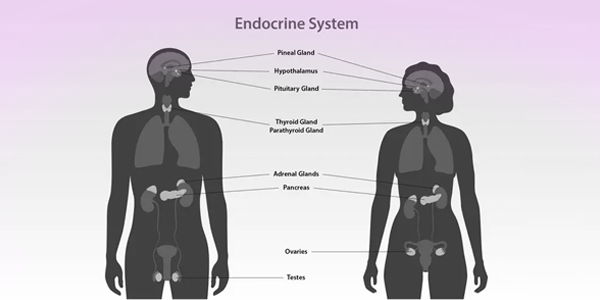

Endocrinology

The endocrine system is a complex network of glands and hormones that regulate vital bodily functions such as metabolism, growth, reproduction, mood, and hormonal balance. Major components of this system include the thyroid, pituitary, adrenal glands, pancreas, ovaries, and testes. When these glands malfunction, it can lead to a wide range of disorders including diabetes, hypothyroidism or hyperthyroidism, polycystic ovary syndrome (PCOS), osteoporosis, hormonal obesity, infertility, and various male and female hormonal imbalances.